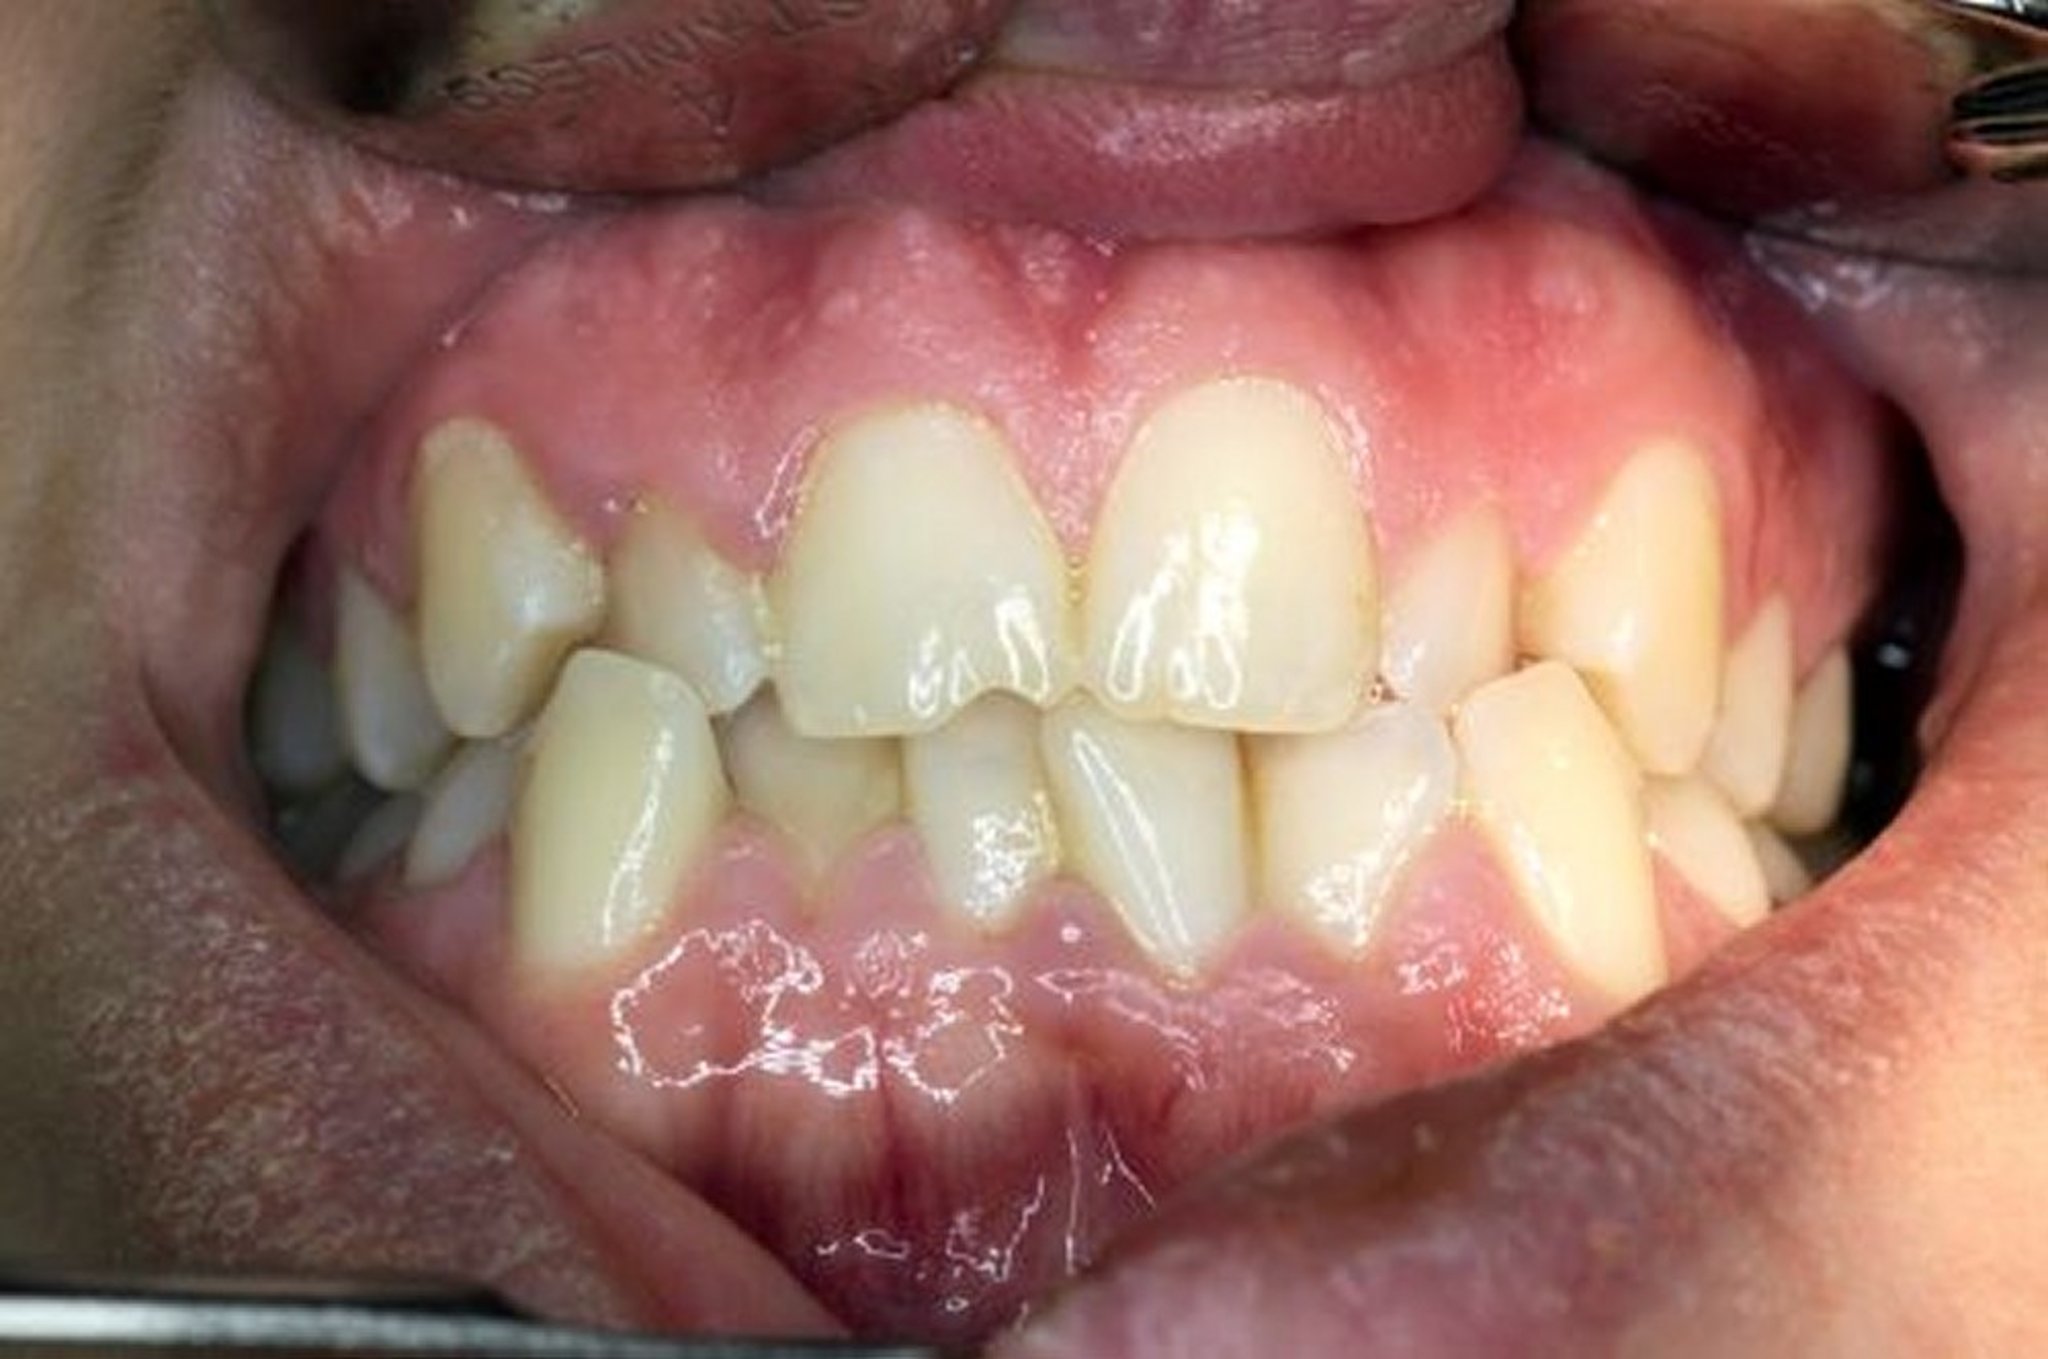

The upper and lower teeth are misaligned as the jaw is closed.

DR ARMEN TARANYAN/SCIENCE PHOTO LIBRARY